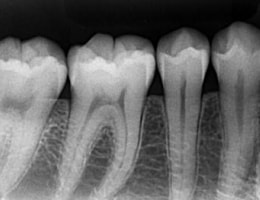

大きなパノラマレントゲンは歯並びなど、全体像をつかむことにも有効的ですが、

現状を詳細に把握するため、小さいレントゲンを10枚撮って診断・治療をしております。

これにより歯石、歯周ポケット等も詳細に把握でき、緻密な治療を提供することが出来ます。